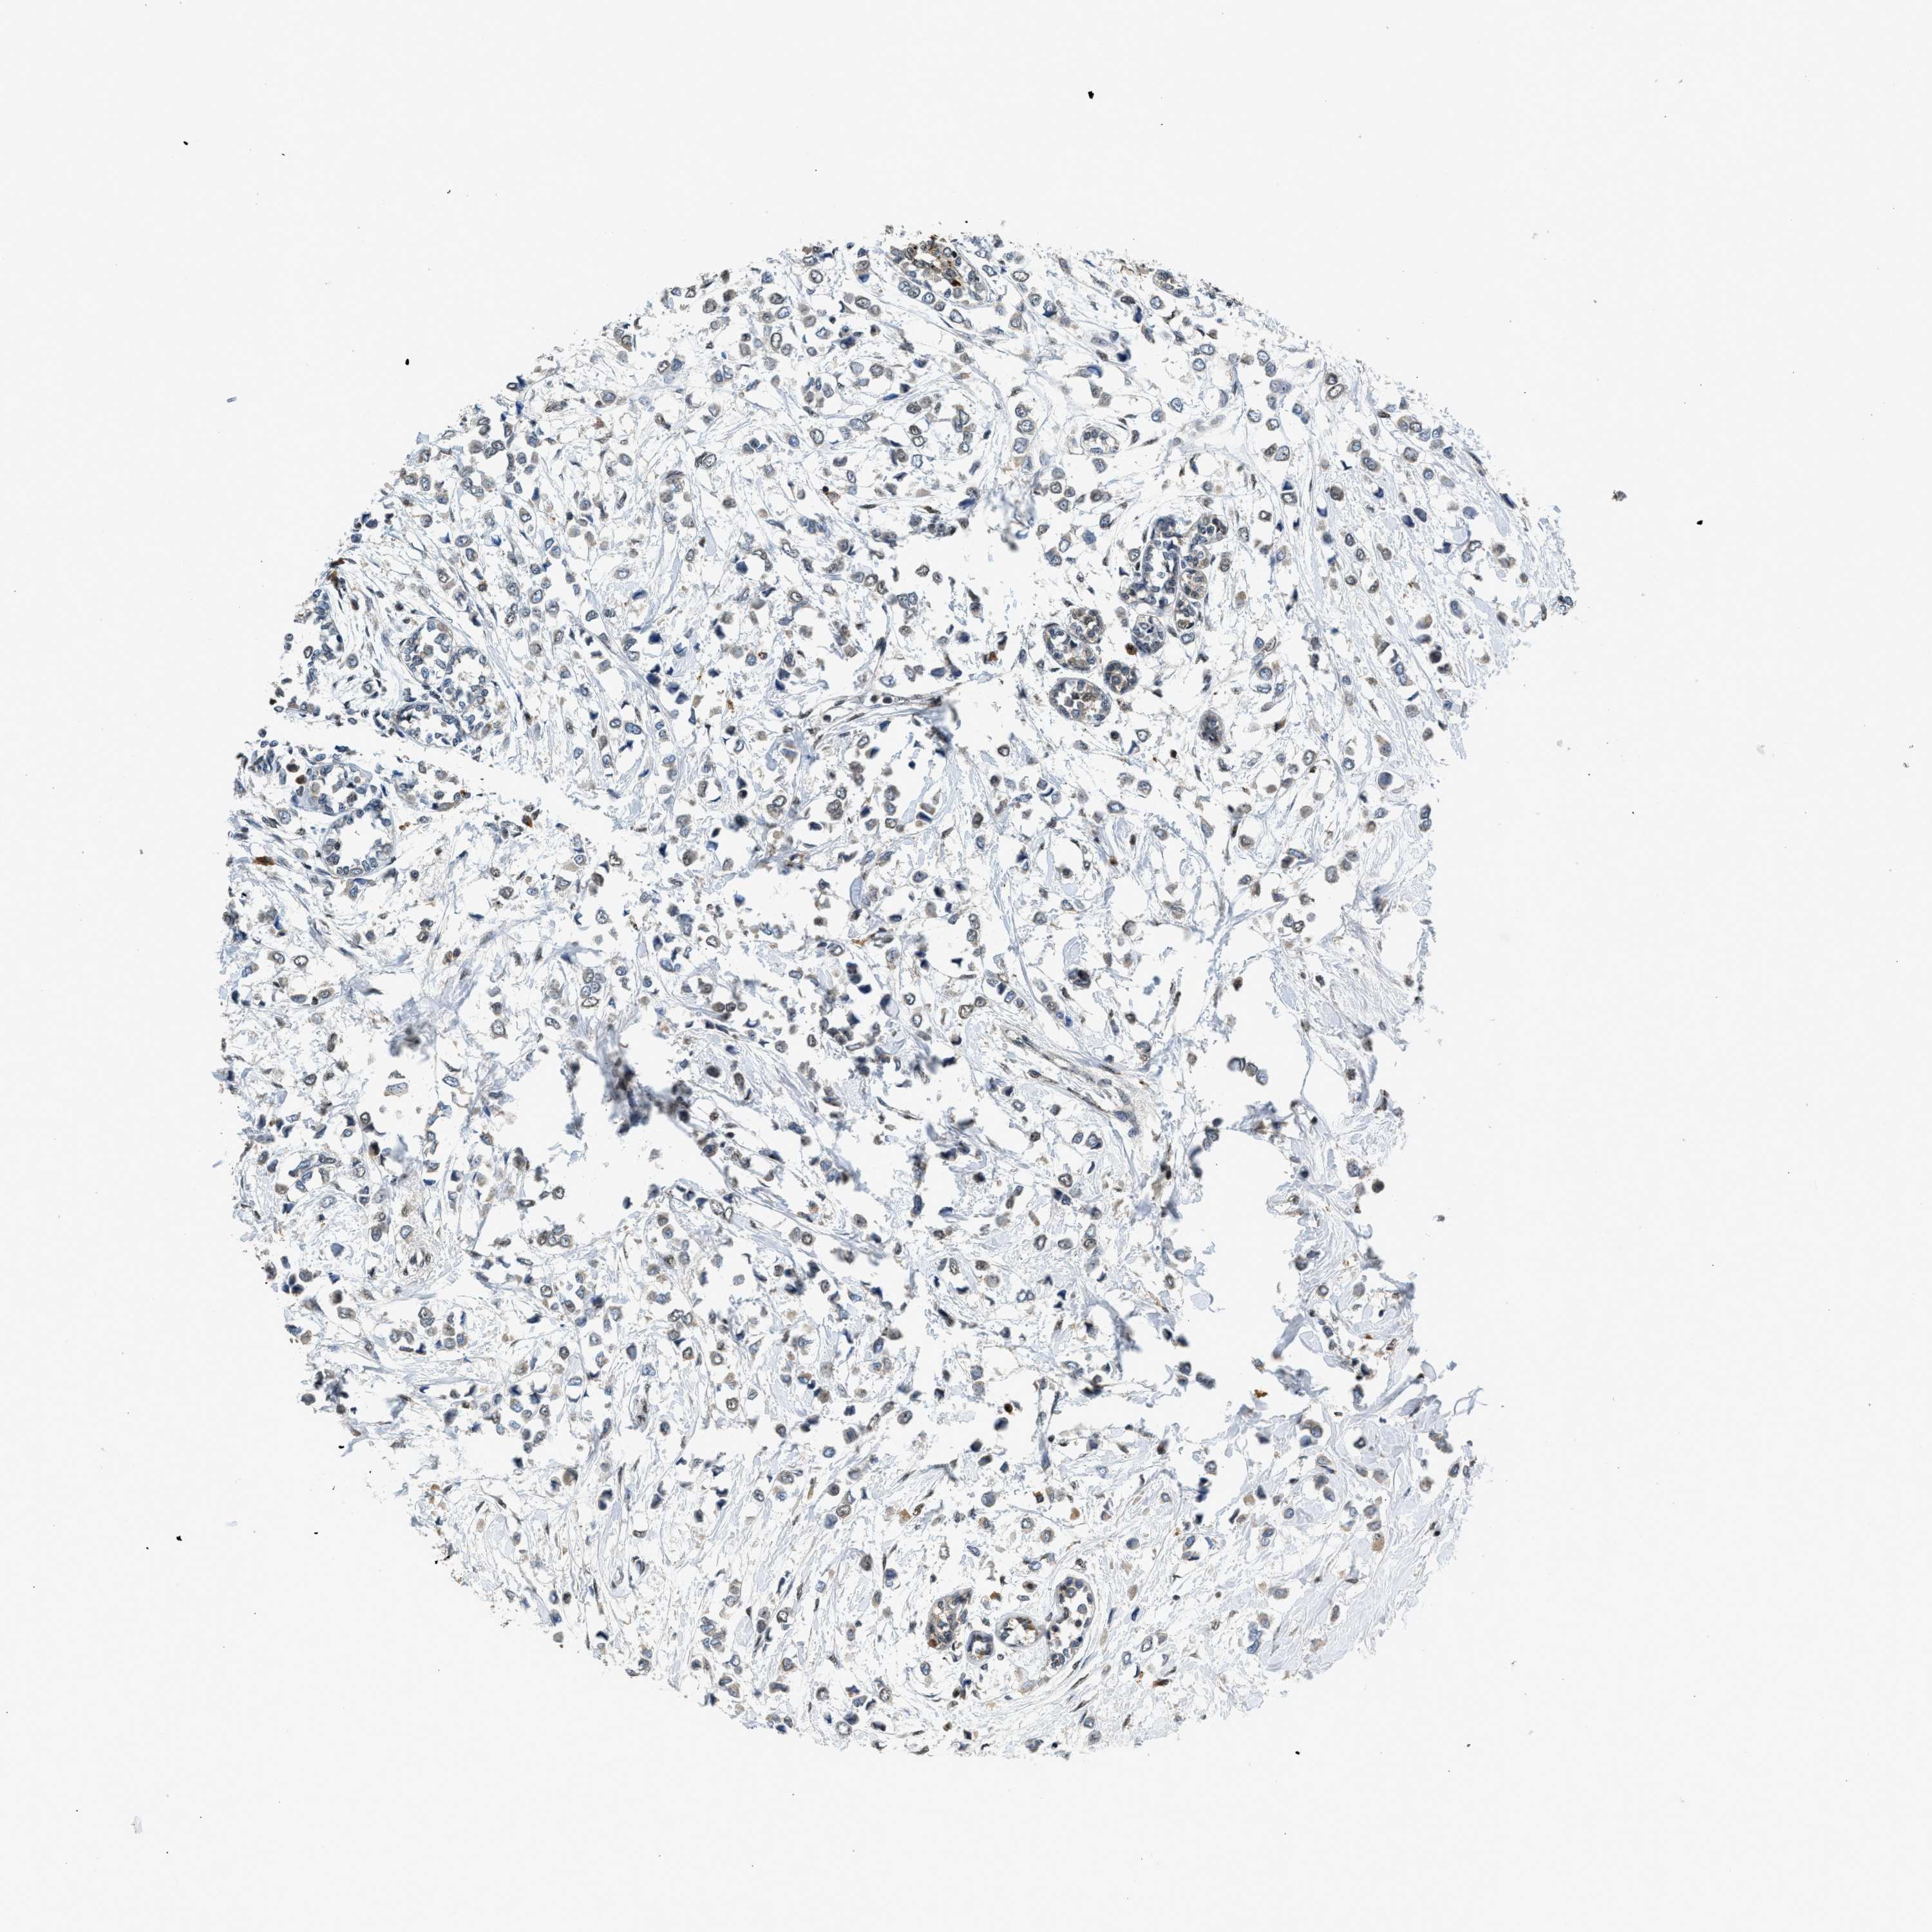

CANCER BREAST CANCER Show tissue menu

BRCA TCGA BRCA VALIDATION PROTEIN EXPRESSION